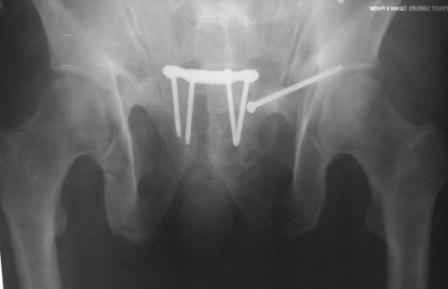

Re: закрытый остеосинтез лонной кости винтом

в архиве нашел подобный случай

С Уважением А.Миронов(Новокузнецк)